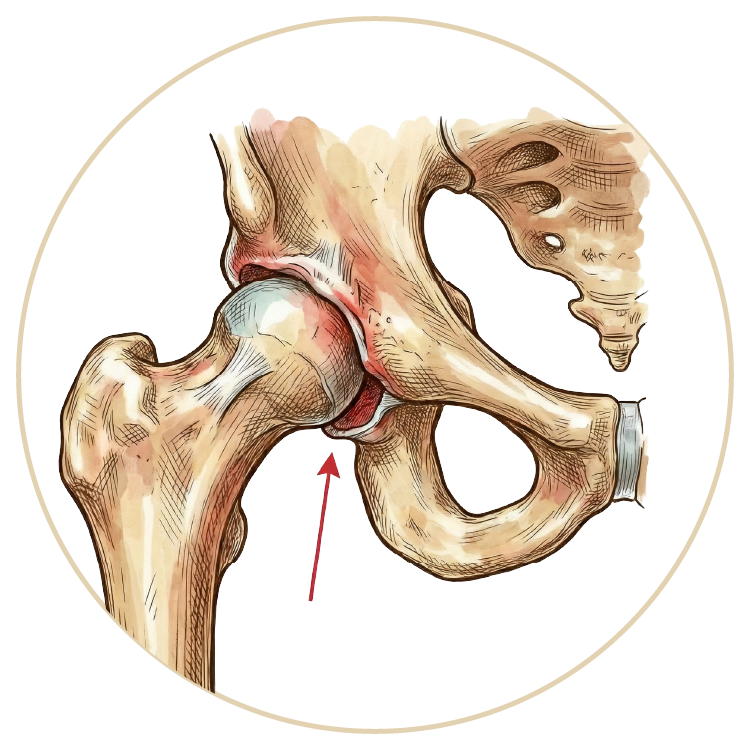

Kalça Hastalıkları ve Tedavileri

Kalça Hastalıkları ve Tedavileri

Kalça Sıkışma Sendromu